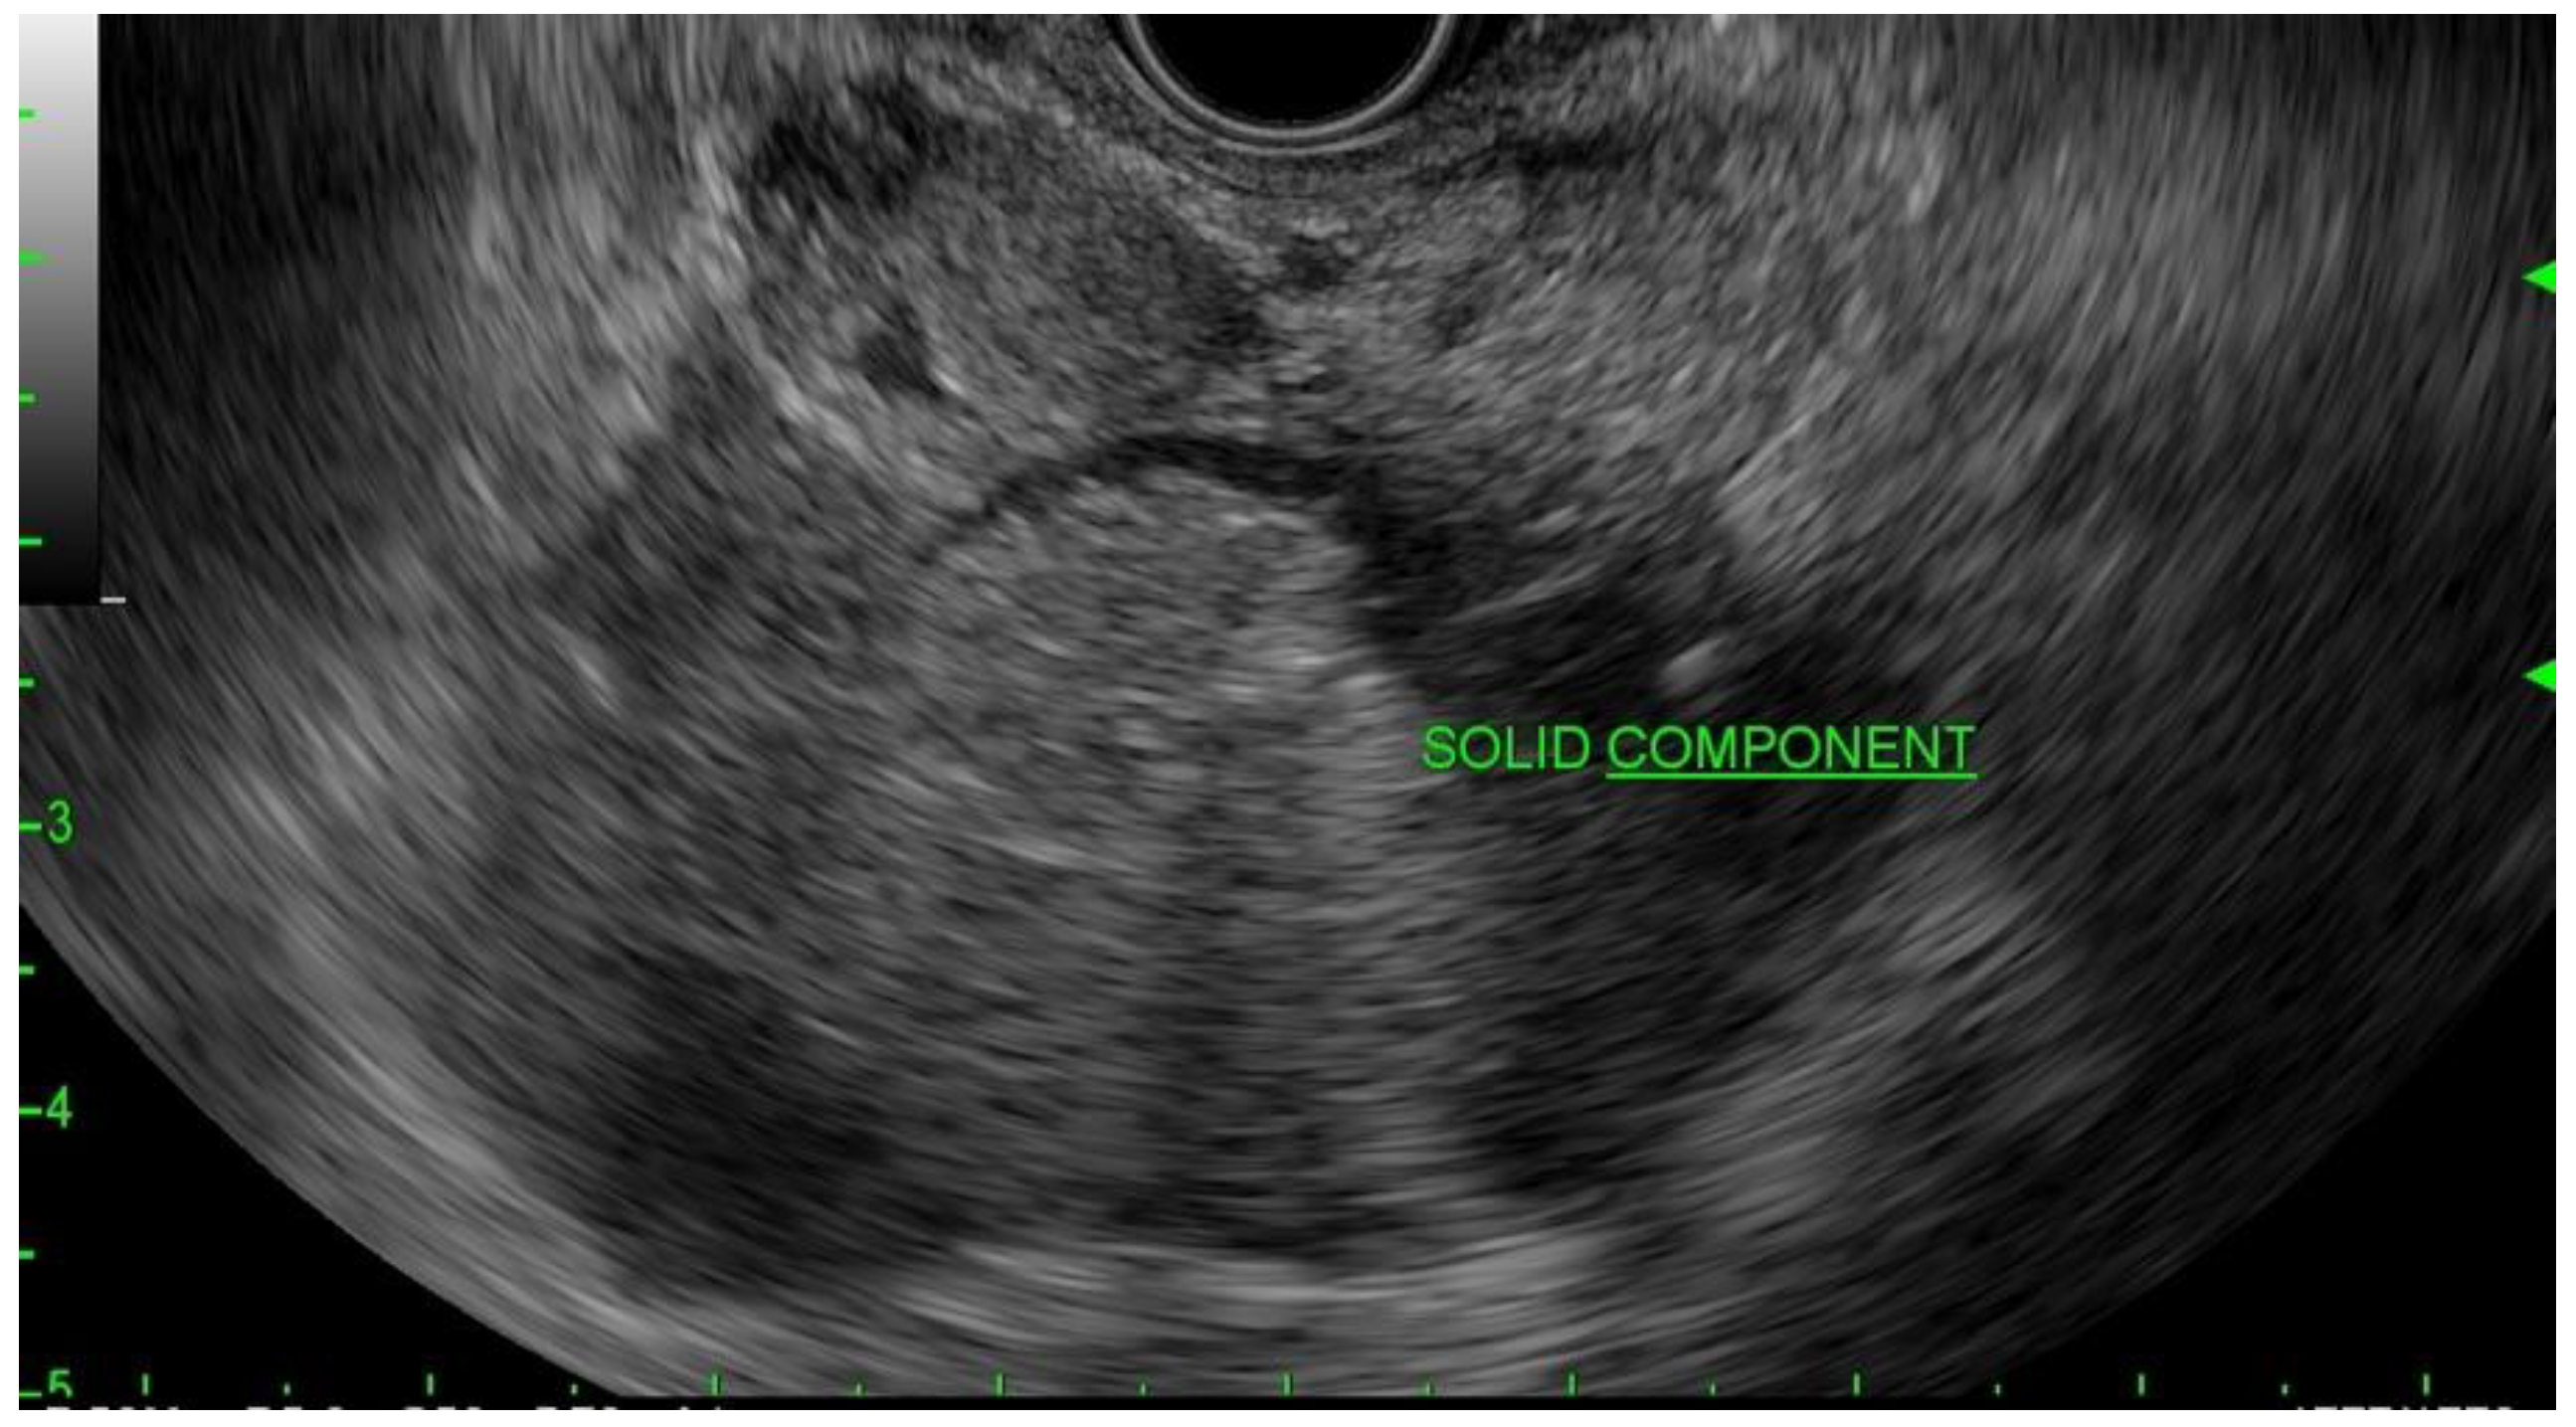

Figure 1.

EUS image of the mural nodule (labeled solid component) in a mucinous cyst.

MCNs usually present in the fifth to seventh decade of life and are almost exclusively in females. Typical imaging characteristics consist of unilocular or septate cysts with wall calcifications (Figure 1). MCNs are defined as having ovarian-type stroma with mucin production. A solid component may suggest malignancy [9]. The aspirate is usually viscous, and the cytology findings consist of columnar cells with variable atypia. On cytology, if cells are present, there are columnar cells with stains positive for mucin. CEA is usually >200 mg/mL in approximately 75% of lesions, and the typical glucose level is usually less than fifty [10]. In a study of 90 resected MCNs, only 10% contained either high-grade dysplasia or pancreatic cancer; however, the reported rate of malignancy ranges from 0 to 34% [11,12,13,14].